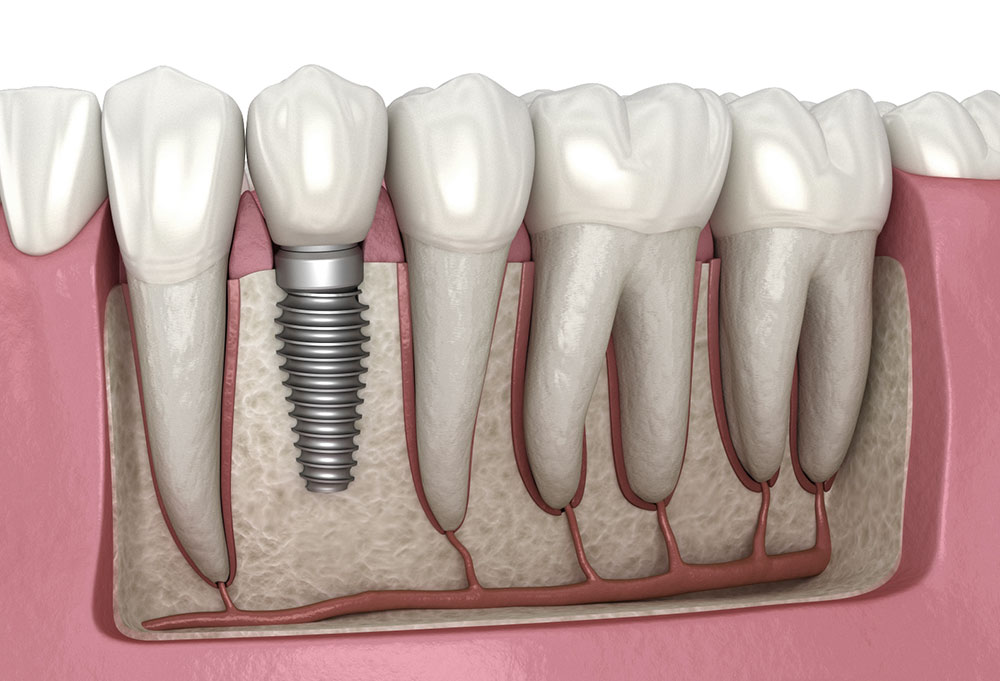

على عكس أطقم الأسنان أو الجسور، تلتحم الغرسات بعظم الفك، مما يوفر حلاً دائماً يمكن أن يستمر لعقود مع العناية المناسبة.

تحفز الغرسات نمو العظام، مما يمنع ترهل الوجه وفقدان العظام المرتبط عادةً بالأسنان المفقودة.

إجراء لطيف طفيف التوغل لوضع دعامة التيتانيوم. التخدير الموضعي يضمن الراحة التامة.

الاندماج العظمي

على مدار 3-6 أشهر، تلتئم الغرسة وتلتحم بعظم الفك لإنشاء أساس صلب.